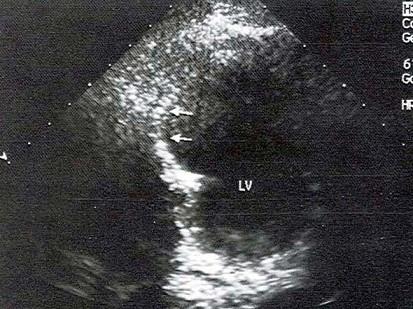

该病例最可能的诊断?(?)A.真性室壁瘤B.假性室壁瘤C.室壁憩室D.扩张型心肌病E.膜部瘤

问题 该病例最可能的诊断?(?)

选项 A.真性室壁瘤 B.假性室壁瘤 C.室壁憩室 D.扩张型心肌病 E.膜部瘤

答案 A